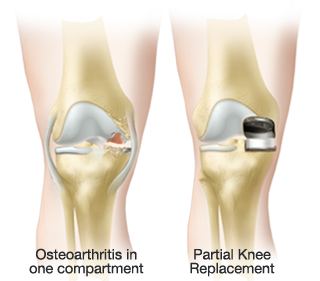

La prótesis parcial de la rodilla es una prótesis especial que está indicado en pacientes con un desgaste muy inicial y con un patrón que afecta solo un compartimiento (interno o externo) de la rodilla. La unicompartimental medial es usada para desgaste entre el fémur y tibia por dentro y la unicompartimental lateral cuando el desgaste entre el fémur y tibia es por fuera. Tiene la ventaja de resecar mucho menos hueso del paciente, así preservando más hueso para el futuro. Además, al mantener la parte biológica del cartílago y la ligamentosa de los cruzados de la rodilla, parece conservar mucho mejor la sensibilidad y la marcha de la rodilla (la propiocepción). También la recuperación de esta cirugía (al ser menos agresiva) es más rápida.

Por tanto, a diferencia de la cadera es posible tratar la artrosis de la rodilla con una gama de protesis según la parte de la rodilla desgastada y la forma de la pierna. Las diferentes protesis para tratar las enfermedades de la rodilla son las prótesis totales cuando toda la rodilla esta gastada y las parciales cuando solo una parte está afectada. La unicompartimental medial es usada para desgaste entre el fémur y tibia por dentro, la unicompartimental lateral cuando el desgaste entre el fémur y tibia es por fuera y la femoropatelar cuando el desgaste es entre el fémur y la patela por delante.